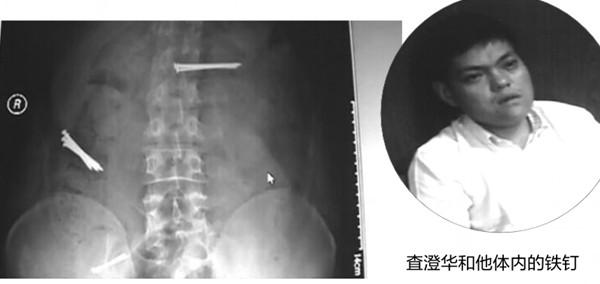

近年来,一位名叫査澄华的男子屡屡出现在全国不少地区,他经常会吞下数枚铁钉,然后向医院或警方求救,但又谎话连篇,编造自己的身世,因此被人在网上冠以“吞钉男”的外号。日前,他出现在蚌埠市,吞下9枚钉子,并要求医院给其注射杜冷丁,遭拒后又悄然离去。

鉴于这名男子有诸多可疑的行为,民警在网上进行了查询,原来,这名“吞钉男”早已被多家媒体报道过,该男子真名叫查澄华,家住江阴华士镇,他因为性格怪异多次离家出走,在流浪期间,他数次用同样的谎言和手法,博得社会关注。

经查询,仅在2012年6月份,査澄华就曾出现在三个地方的医院,每次都是因吞下钉子来求救,足迹遍及江浙一带,这些地方的媒体都对其进行过报道。 6月12日,他曾出现在浙江省中医院,声称被一个犯罪团伙控制,被迫吞下钉子;6月下旬,他以被强迫吞钉为由,先后向无锡市区和江阴市的两家医院求救;7月4日,他出现在南通市,自称姓李,是杭州人,被人骗到盐城从事传销活动,因拒绝加入被强迫吞下铁钉;7月9日,他来到常州,声称被养父母强迫吞下铁钉。